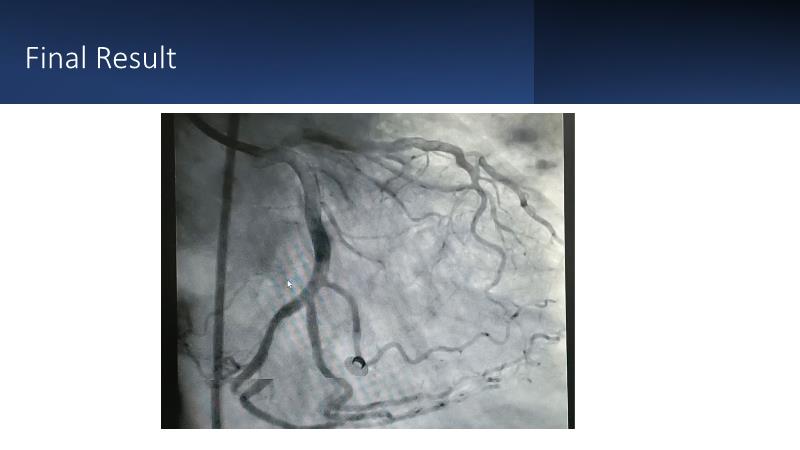

Next generation of DES technology, what it's all about? Find out in this session where experts will present complex cases from around the world and discuss the new indications for which they can be used.

• To know why and how a fusion coating of DES+DCB stent platform is effective for the treatment of cardiovascular disease in diabetes mellitus patients via case presentations

• To understand why you can count on customised drug delivery platform of DES+DCB in complex settings with imaging-based evidence through case presentations

• To gain an insight on how the next generation no-polymer DES+DCB stent platform will address the unmet needs in coronary artery disease patients